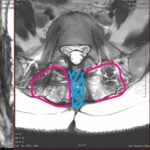

Printre acestea, RMN-ul (interpretare RMN) reprezintă o metodă de imagistică avansată utilizată pentru a identifica inflamația și modificările structurale la nivelul articulațiilor sacroiliace.

Aceasta oferă o imagine detaliată a țesuturilor moi și a structurilor osoase, permițând medicului să formuleze un diagnostic precis și să stabilească un plan de tratament adecvat pentru pacient.